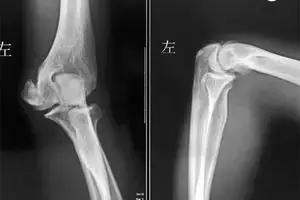

肘关节不稳是一种常见的损伤,包括肘关节的半脱位和完全性脱位,主要临床表现是局部疼痛、关节弹响、纹锁等非特异性症状。肘关节不稳包括简单的内侧、外侧不稳定及严重骨折脱位造成的复杂不稳定。

根据创伤是否累及周围的骨性结构,分为单纯性肘关节不稳和复合性肘关节不稳。

单纯性肘关节不稳:应立即复位,对于后外侧脱位的患者,复位后患者取仰卧位。复位后肘关节固定于屈肘90°,副韧带损伤情况决定前臂处于何种体位。

复合性肘关节脱位:骨折最常累及桡骨小头和冠状突,故治疗涉及脱位的复位和骨折的治疗。治疗首先针对骨折的整复和内固定以及周围韧带的修复和重建,石膏外固定于功能位。复位固定后若仍存在关节不稳定,应行韧带修复或重建术,根据情况有铰链肘外支架固定、全关节置换等治疗方法。